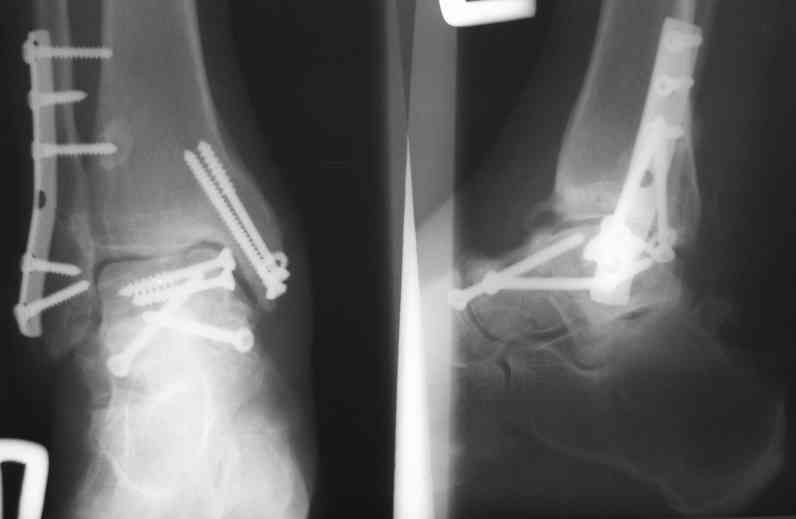

В Вашей ситуации мы произвели открытую репозицию и фиксацию металлоконструкциями. Все зажило первично, посттравматического дефартроза избежать не удалось. Пациент от артродезирующих операций в отдаленном периоде отказался.